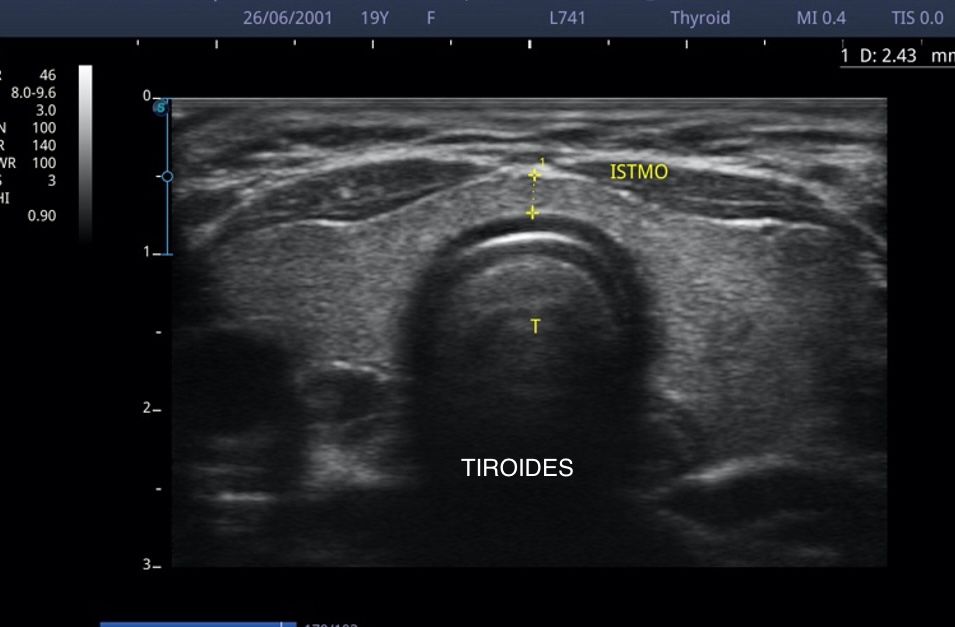

Médico general con 15 años de experiencia, master en enfermedades infecciosas y antibioticoterapia por parte de la Universidad Cardenal Herrera en Valencia, ademas de diversos diplomados en el área de Infectología y Parasitología, Urgencias, Imagenología y Medicina del Trabajo. He laborado en Hospitales y Clínicas en el área de Urgencias, en Laboratorios realizando estudios de Imagen, en especifico ultrasonidos de todo tipo desde básicos hasta avanzados incluidos los obstétricos estructurales, en Secretaría de Salud del Estado de Querétaro realizando ultrasonidos obstétricos para la detección de malformaciones en los tres trimestres del embarazo en diversos centros de salud, como médico de Empresas en el campo de Salud Laboral y actualmente en este consultorio en donde para su mejor atención y siempre buscando integrar la mayoría de las herramientas diagnosticas cuento con equipo de ultrasonido como apoyo en la exploración del paciente o como servicio diagnostico por imagen, realizo ultrasonidos convencionales (hepatobiliar (hígado, páncreas, vesícula y bazo), vías urinarias, ginecológico abdominal y transvaginal, tiroideo, prostático, testicular, pared abdominal) y especializados (dopler obstétrico en los 3 trimestres de embarazo), musculoesquelético en lesiones deportivas. También cuento con un equipo de electrocardiograma de 12 derivaciones para monitoreo completo del funcionamiento cardiaco, espirometria para evaluar la función pulmonar en la consulta, pruebas rápidas que se realizan en consultorio para detectar de forma mas precisa enfermedades infecciosas como Influenza A y B, covid19, infecciones urinarias, dengue, zika, chikungunya. Cuento con diversas vacunas para prevención de enfermedades. Siempre con el objetivo de dar el mejor servicio y atención a su salud. Lo espero en consulta para escucharlo y estudiar su caso de la forma más completa posible, estoy seguro de que tendremos las mejores opciones para su tratamiento. Mi tranquilidad es que usted se vaya con todas sus preguntas e inquietudes resueltas.

• Ultrasonido diagnóstico